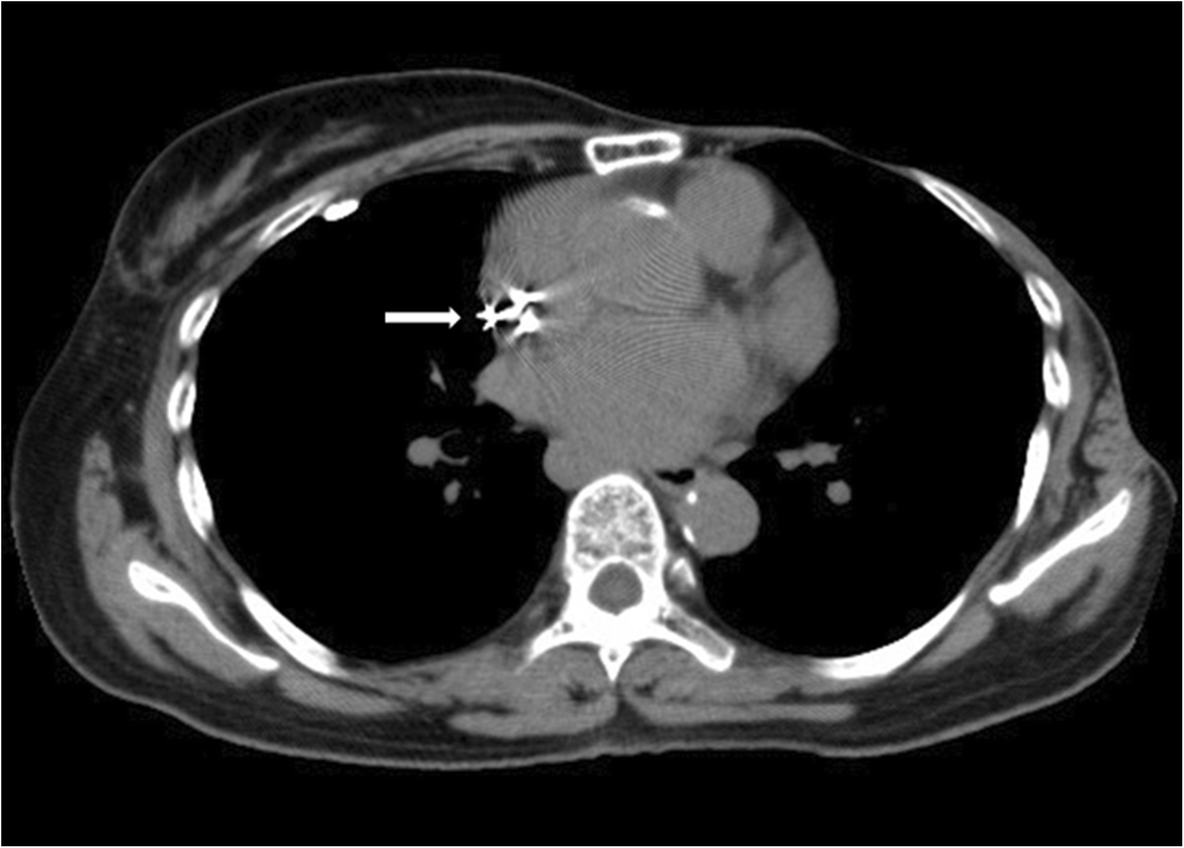

from jaclinicalreports.springeropen.com

Sudden onset pacemakerinduced diaphragmatic twitching during general Chest Twitching With Pacemaker The twiddler syndrome is an uncommon cause of pacemaker malfunction, in which twisting or. Muscle twitching caused by a pacemaker is not uncommon. An emergent temporary pace maker. Involuntary muscle contraction caused by extracardiac stimulation is a rare. I started to get a strong and. Has anyone had any experiences with a muscle twitch on the chest wall over the. Chest Twitching With Pacemaker.